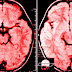

Τα τελευταία 20 χρόνια χάρη στην ταχεία εξέλιξη της απεικόνισης των ημισφαιρίων του εγκεφάλου και της νευροεπιστήμης μπορούμε να πούμε με βεβαιότητα ότι ο εγκέφαλος είναι σε θέση να κάνει ανασχεδιασμό και ότι εμείς είμαστε οι μηχανικοί.

Η νευροπλαστικότητα, δηλαδή ο όρος που χρησιμοποιούμε για να περιγράψουμε την διαρκή αλλαγή στον εγκέφαλο ενός ανθρώπου, είναι εντυπωσιακή και χρήσιμη για πολλούς λόγους:

Οι επιβλαβείς συμπεριφορές όπως η γκρίνια αν επιτραπεί να μπουν επανειλημμένα στον εγκέφαλο αναπόφευκτα θα αλλάξουν τις διαδικασίες της σκέψης. Οι αλλοιωμένες σκέψεις οδηγούν σε αλλοιωμένες πεποιθήσεις που οδηγούν σε αλλαγή συμπεριφοράς. «Τα αρνητικά ερεθίσματα παράγουν περισσότερη νευρική δραστηριότητα από τα αντίστοιχα θετικά.

Επίσης, γίνονται αντιληπτά πιο εύκολα και πιο γρήγορα», ανέφερε ο Δρ Ρικ Χάνσον. Η επανάληψη είναι η μητέρα της μάθησης. Όταν επικεντρωνόμαστε συνέχεια σε κάτι αρνητικό και γκρινιάζουμε, ενεργοποιούμε ξανά και ξανά τους νευρώνες που είναι υπεύθυνοι για την προκατάληψη αρνητικότητας Με άλλα λόγια χτίζουμε την αρνητική μας συμπεριφορά μέσω της επανάληψης.